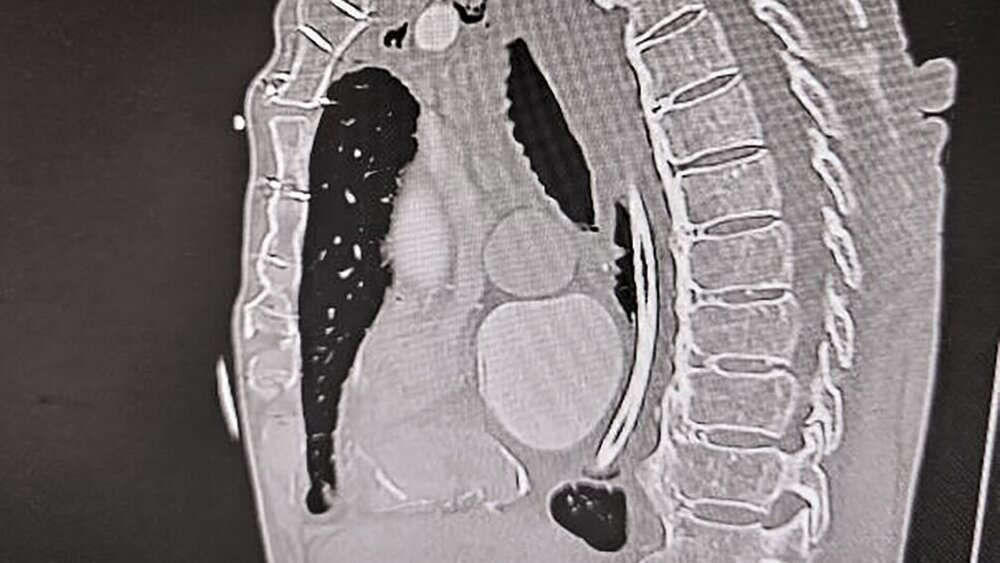

Während der Ösophagoskopie kam es zu einer traumatischen Perforation der Speiseröhre bei etwa 22 cm ab Zahnreihe. Zudem wurde während der Untersuchung ein anscheinend stark gelockertes dentales Implantat unbemerkt entfernt und nach aboral disloziert, bis es durch die simultan entstandene Perforation des Ösophagus in das Mediastinum verlagert wurde. Da eine intraoperative Verletzung des Ösophagus nicht ausgeschlossen werden konnte, wurde unmittelbar postoperativ eine Computertomografie von Hals und Thorax veranlasst. Diese zeigte rechtsseitig paraösophageal abgrenzbare Luft im Mediastinum, beginnend vom Kieferwinkel bis kurz kranial des Aortenbogens (Abbildung 1) sowie einen metalldichten Fremdkörper im Bereich des oberen Mediastinums (Abbildungen 2 und 3).